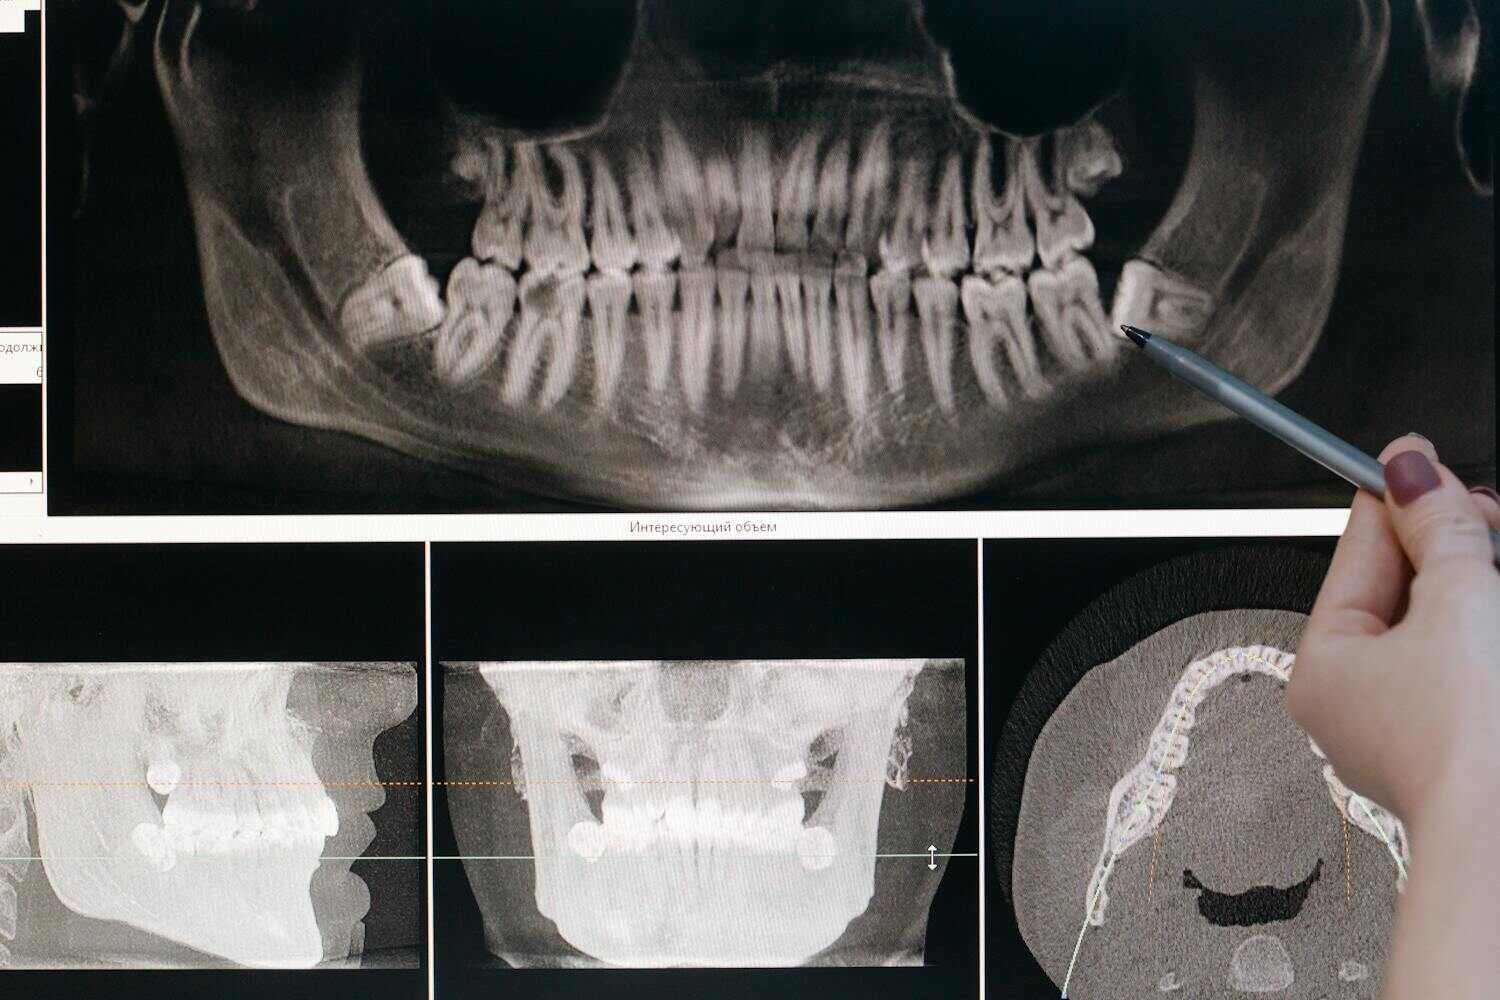

数字口腔学硕士 - 显示器展示牙齿全景数字影像进行精准诊断分析 - ISEIE中国